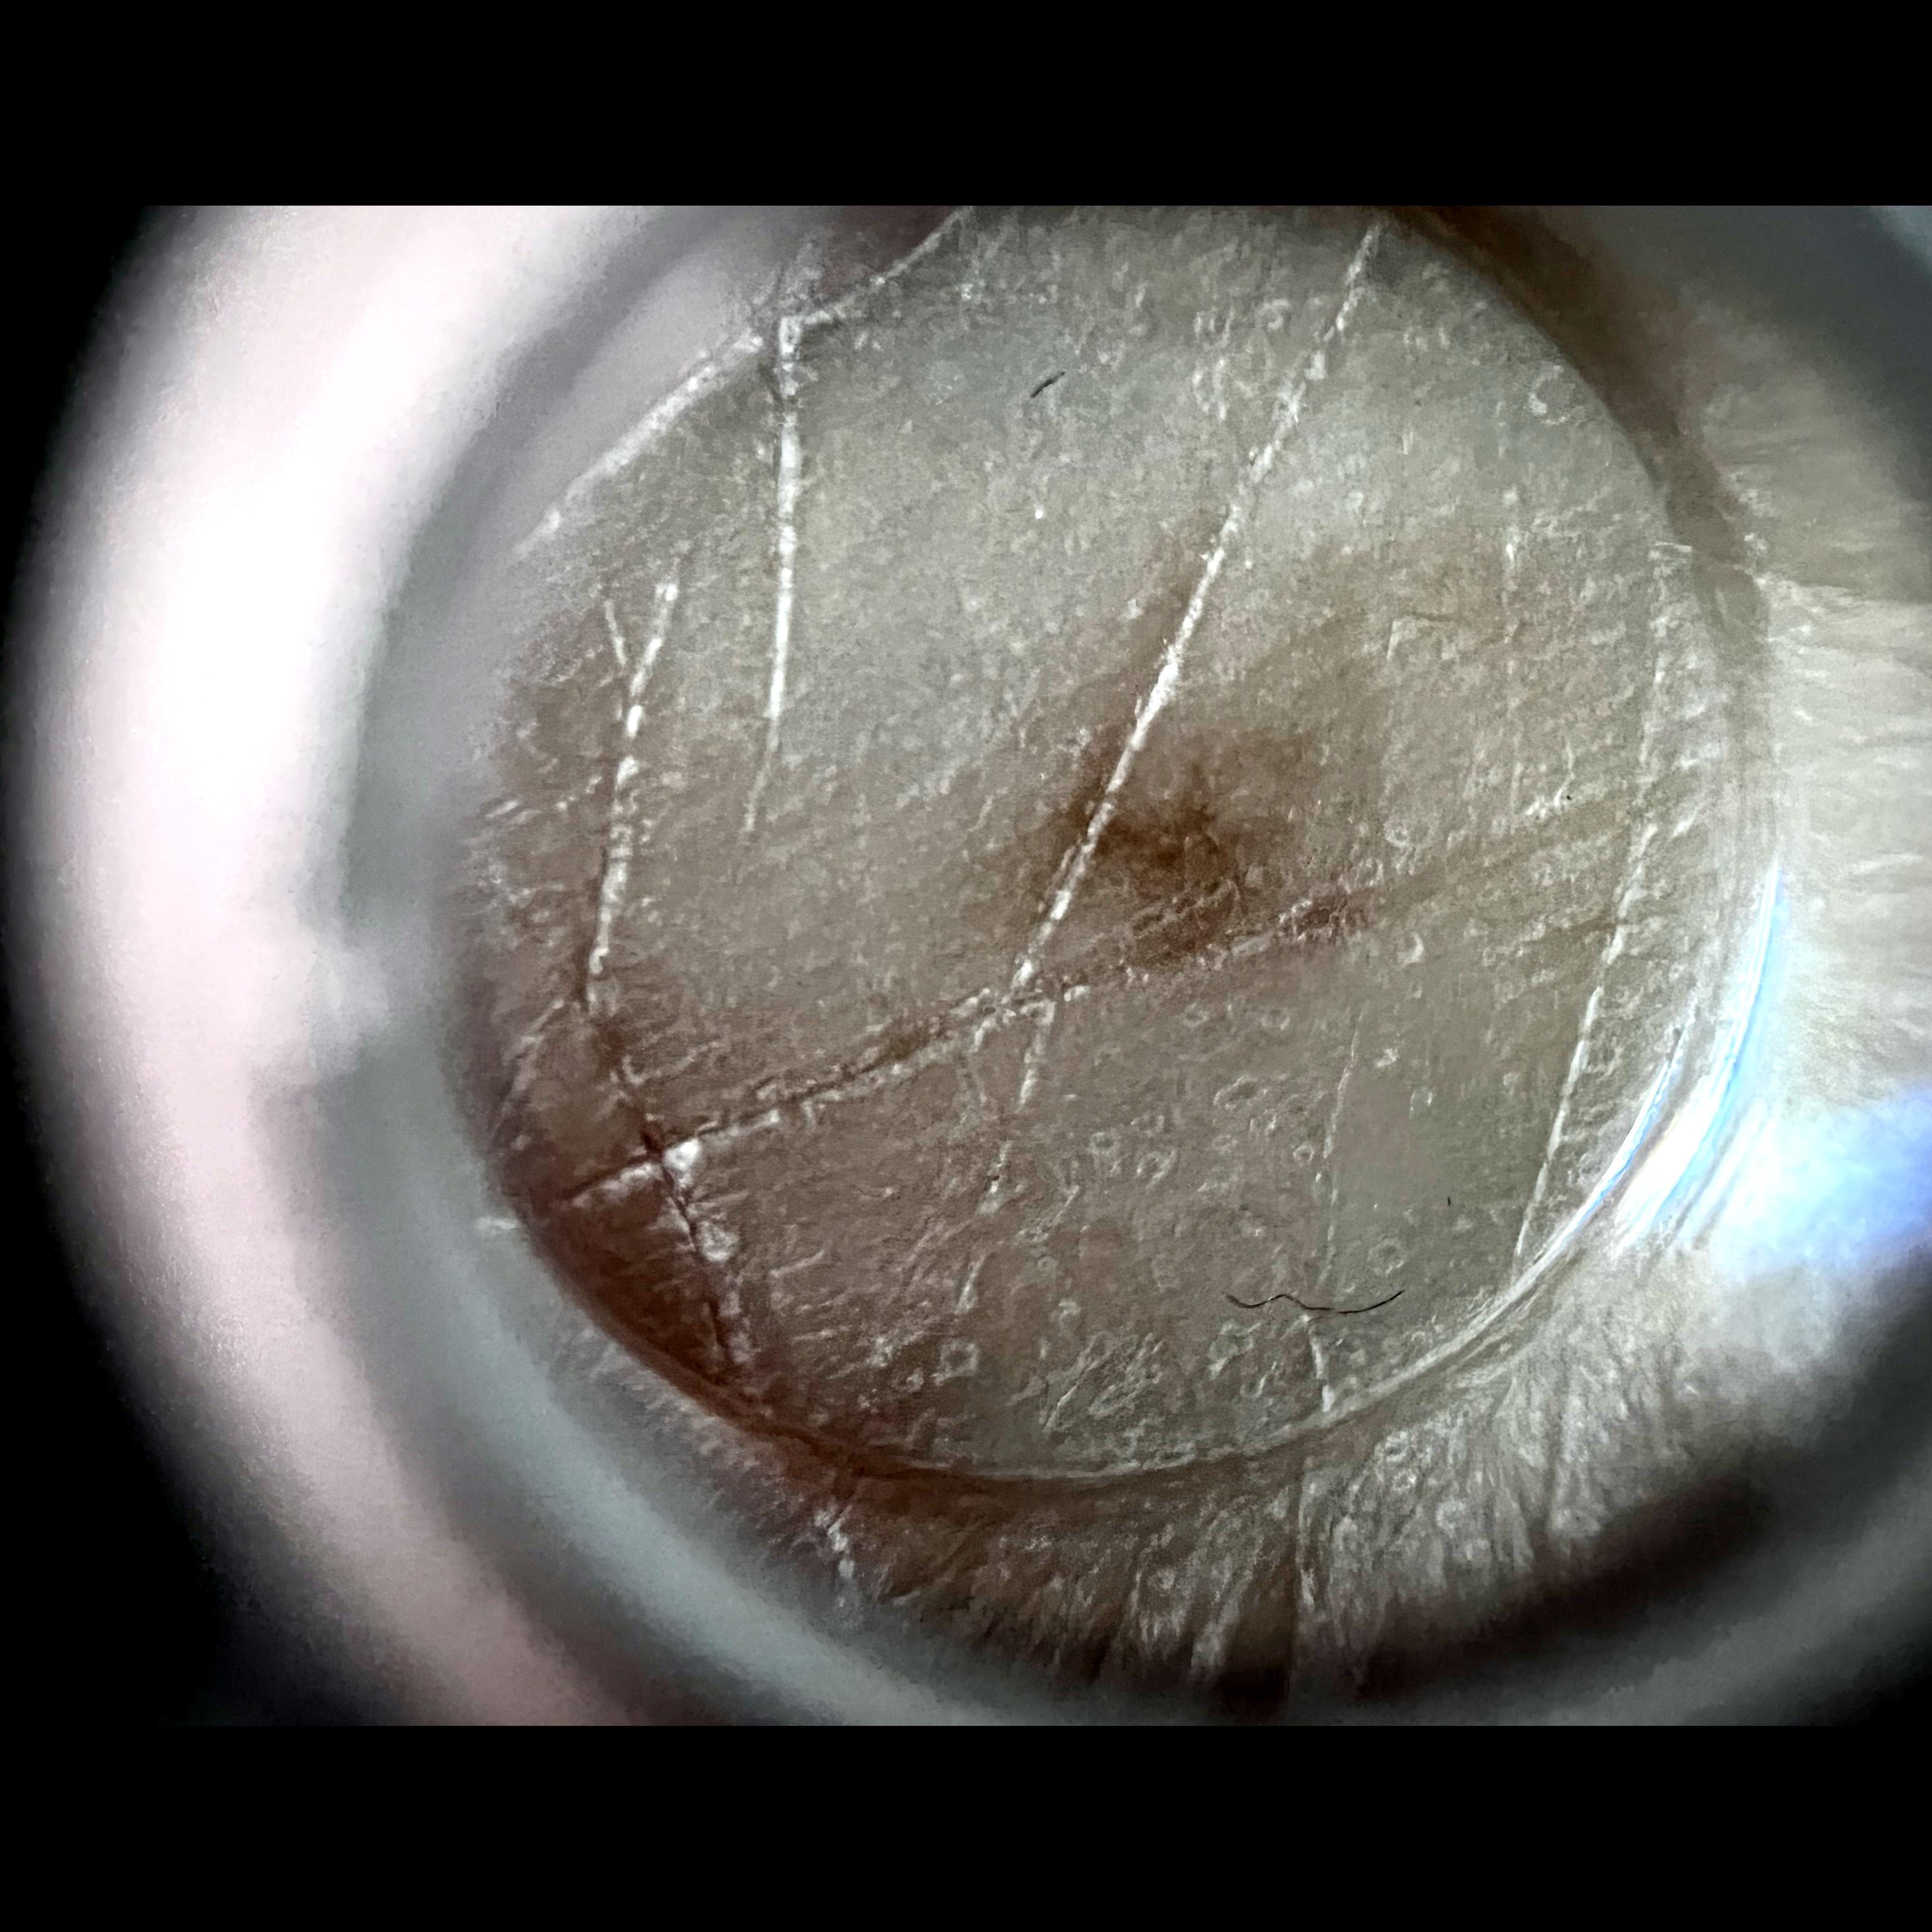

ISIC_7213120

image_type dermoscopic